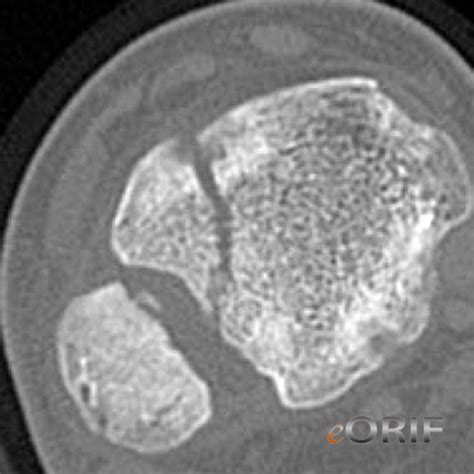

Tillaux Fracture S89.129A 823.80 | eORIF

Tillaux Fracture S89.129A 823.80 | eORIF from eorif.com